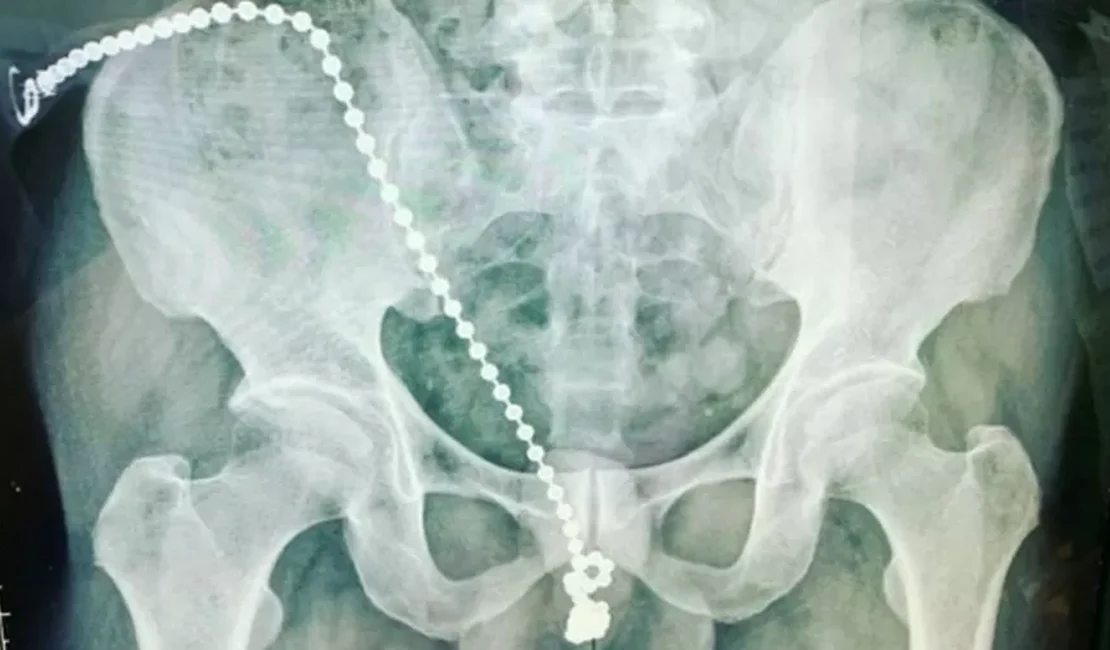

A corrente de bolinhas, de tamanho considerável, estava embutida dentro de seu pênis

Coisa que os médicos só descobriram após submete-lo a um procedimento cirúrgico de emergência, para retirar o objeto. A corrente de bolinhas, de tamanho considerável, estava embutida dentro de seu pênis, e ele não conseguia removê-la por medo de se machucar ainda mais. Ele também não conseguia ir ao banheiro.